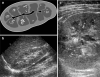

ARPKD/CHF is an inherited disease characterized by non-obstructive fusiform dilatation of the renal collecting ducts leading to enlarged spongiform kidneys and ductal plate malformation of the liver resulting in congenital hepatic fibrosis. ARPKD/CHF has a broad spectrum of clinical presentations involving the kidney and liver. Imaging plays an important role in the diagnosis and follow-up of ARPKD/CHF. Combined use of conventional and high-resolution US with MR cholangiography in ARPKD/CHF patients allows detailed definition of the extent of kidney and hepatobiliary manifestations without requiring ionizing radiation and contrast agents.